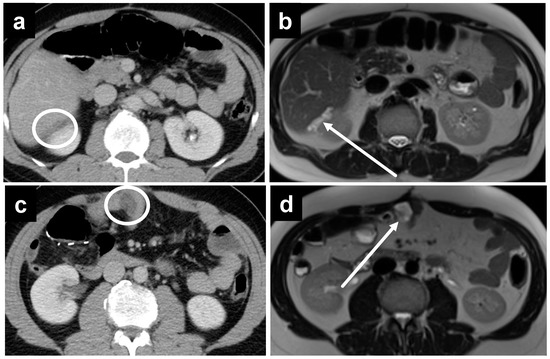

3.2. PSM Detection